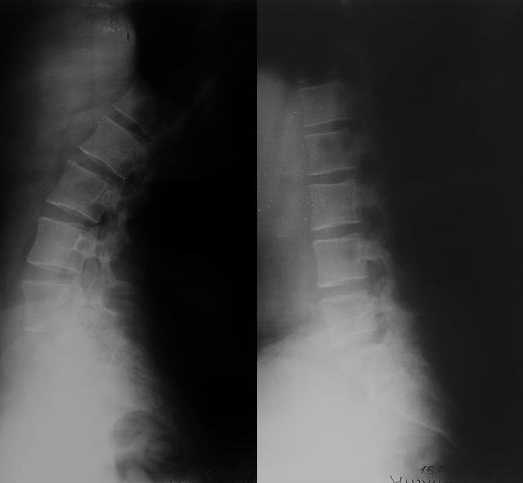

Глубокоуважаемые Сергей и Юрий Алексеевич. благодарю Вас за проявленный интерес с к моей

просьбе. досылаю КТ, фуккциональные Р-граммы пояснично-крестцового отдела позвоночника, фото пациентки.